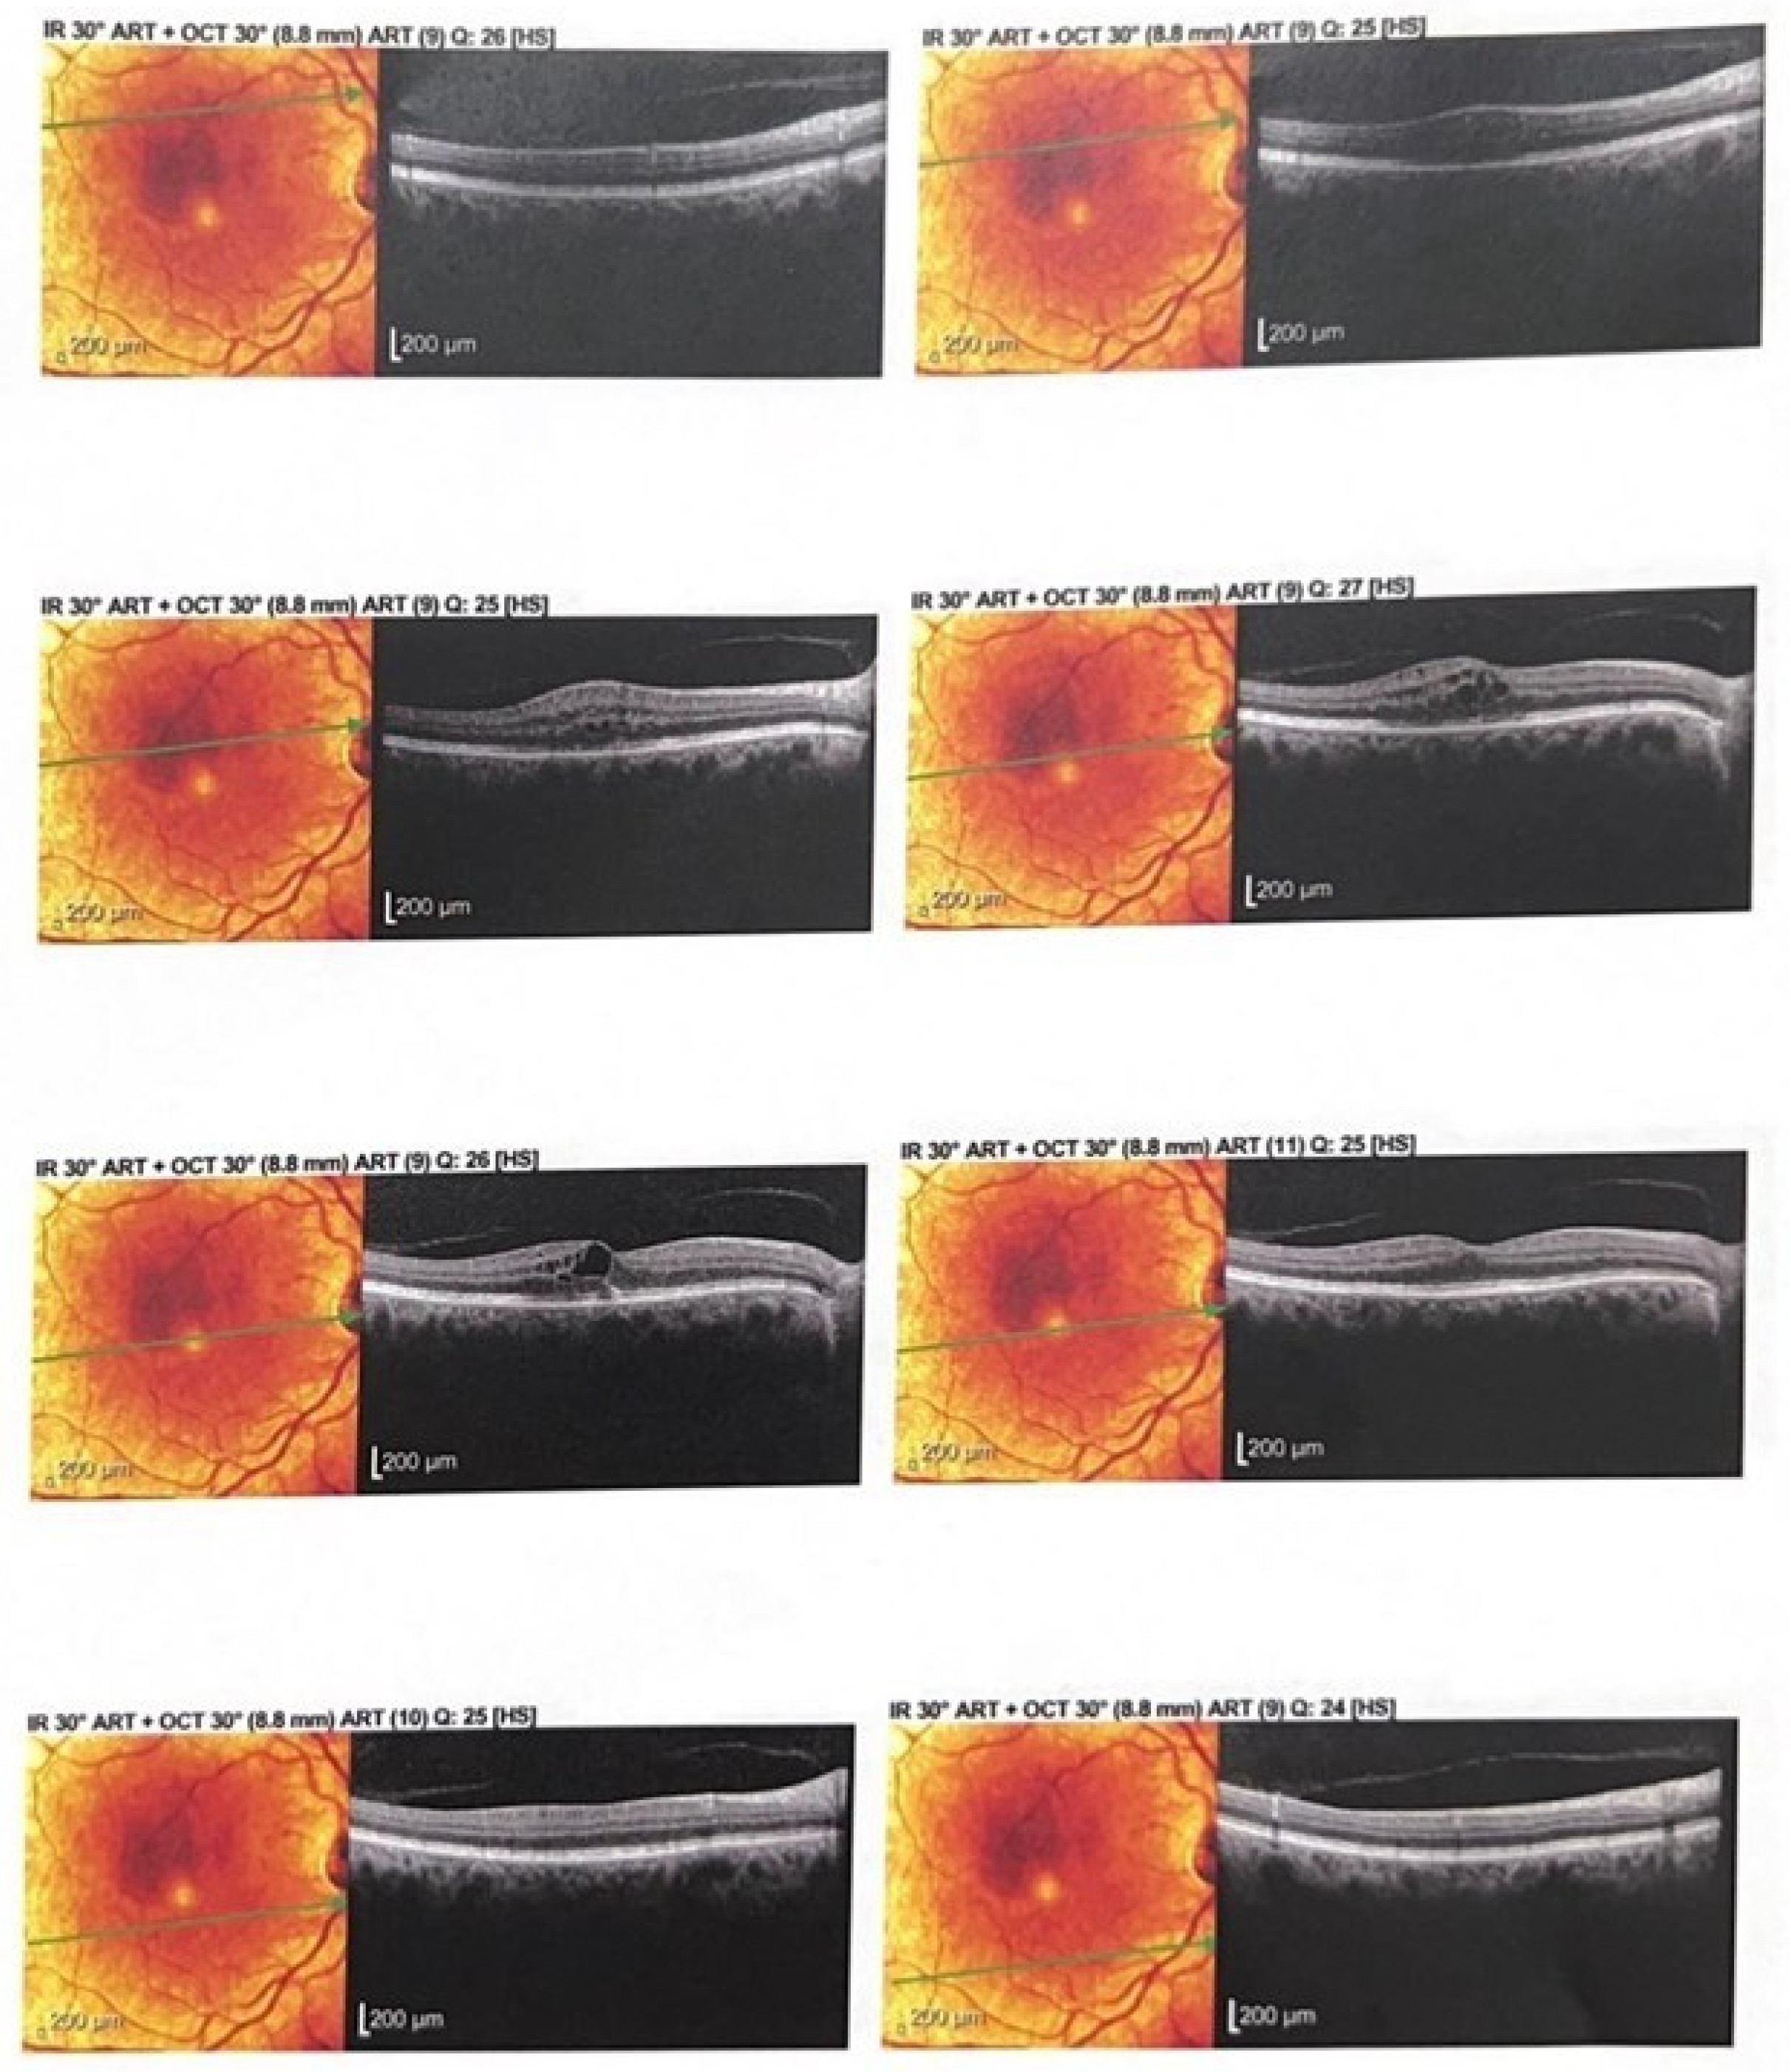

2.4. Figures